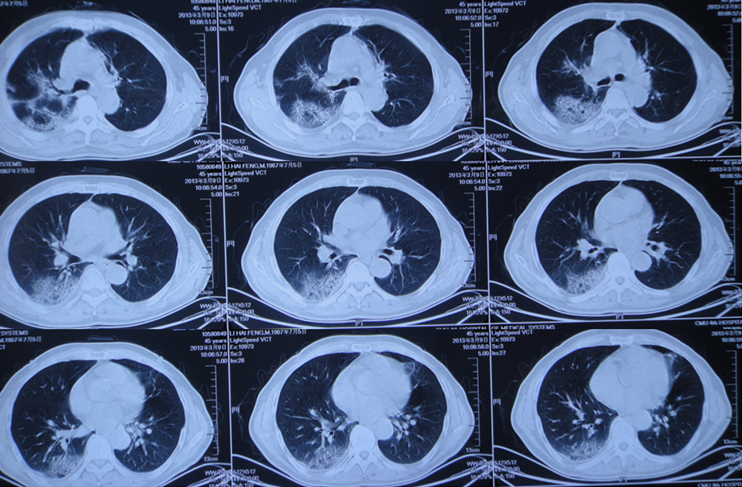

对于急性重型ILD,一定要做到早期识别、早期诊断和早期治疗。我们团队救治成功的病例基本上是在1周之内开始大剂量糖皮质激素治疗。这是我们近期收治的病例,有上呼吸道感染的前驱症状,胸部CT可见明显实变,磨玻璃影,小叶间隔增厚,患者快速进展至呼吸衰竭。

气管插管后完善病原学筛查,尽快给予皮质激素冲击治疗,1周后,患者胸部CT可见病变明显缓解,患者于第10天拔管,后续情况非常稳定。对此类患者,只有平安度过急性期,才有机会进行后续治疗,患者也才能获得良好的预后。